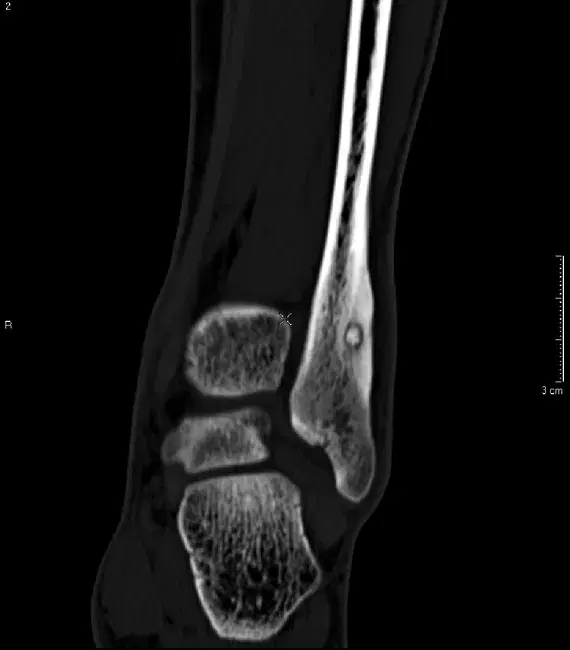

- образни изследвания: рентгенография често е първото проведено изследване, като може да покаже ограничена зона на склероза в кортикалната кост. Нидусът невинаги е ясно видим, особено в ранните стадии. Метод на избор за поставяне на диагнозата е компютърната томография, при която ясно се визуализира централният нидус (малка лезия с по-ниска плътност, често с централна калцификация, заобиколена от изразена реактивна склероза). Особено полезна е при атипични локализации и за прецизно планиране на лечението. При някои пациенти може да се наложи и назначаване на ядрено-магнитен резонанс

Изображение: Компютърна томография на глезена, показваща склеротична лезия в долната фибуларна метафиза. Видим централен склеротичен нидус с правилен тънък остеолитичен ореол. Характеристиките са типични за остеоиден остеом. Кейс на Хани М. Ал Салам, Radiopaedia.org rID: 8506 ; използван под Creative Commons License.